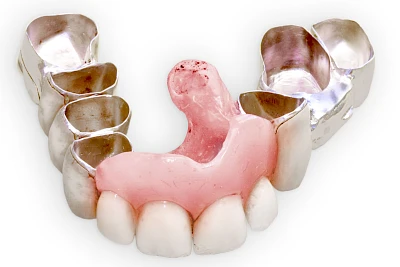

Heute werden in Deutschland Menschen mit Lippen-Kiefer-Gaumenspalten bereits ab Geburt von Experten verschiedener Fachrichtungen (Mund-Kiefer-Gesichtschirurgen, Kieferorthopäden, Logopäden) betreut, damit entsprechende Korrekturen schon frühzeitig erfolgen können. Gerade jedoch bei älteren Menschen ist dies nicht immer geschehen. Diese Menschen tragen häufig technisch aufwendige Zahnprothesen.